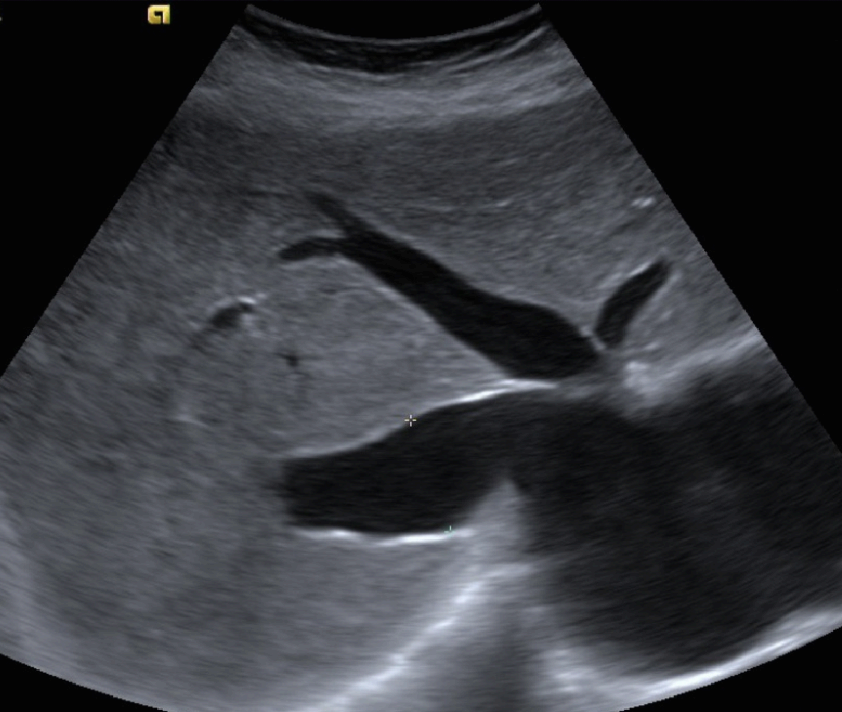

- 하대정맥(IVC) 및 간정맥(hepatic vein)의 확장

- 플레이보이 귀징후(playboy bunny figure)

- 간정맥이 14mm 이상 학장된 상태

- 정상인은 심흡기시 간정맥의 직경변화가 있지만, 울혈성 간질환에서는 간정맥의 직경변화가 없다.